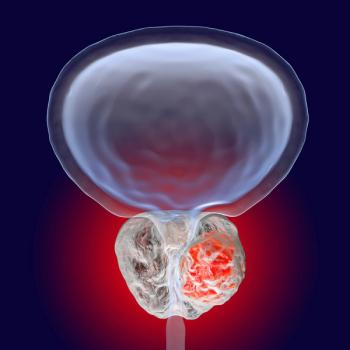

Based on durable response data, TAR-200 has been given priority review for the treatment of patients with high-risk non–muscle-invasive bladder cancer.

The combination of apalutamide to carotuximab showed early signs of tolerability in patients with metastatic castration-resistant prostate cancer.